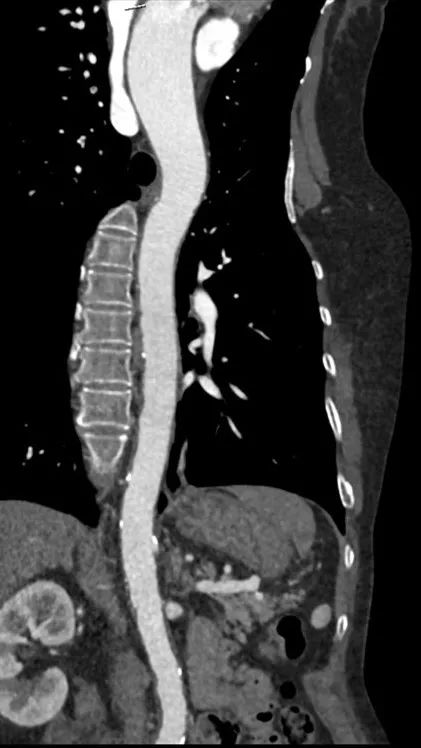

病例荟萃第一期|张瑞岩:Telescope™导引延长导管应用高风险冠脉TAVR一例

张瑞岩 上海交通大学医学院附属瑞金医院

主动脉

右股

左股

术后1w——冠脉CTA